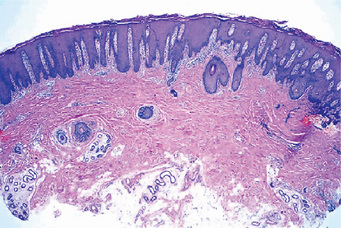

Histopathologic examination of lesional tissue is the most relevant investigation in cases of OLP. Typical findings include hyperparakeratosis or hyperorthokeratosis with thickening of the granular layer, acanthosis with intracellular edema of the spinous cells in some instances, the development of a ‘saw tooth’ appearance of the rete pegs. Band-like subepithelial mononuclear infiltrate consisting of T-cells and histiocytes; increased numbers of intraepithelial T-cells; and degenerating basal keratinocytes that form colloid (Civatte, hyaline, cytoid) bodies, which appear as homogenous eosinophilic globules are consistently seen.

Degeneration of the basal keratinocytes and disruption of the anchoring elements of the epithelial basement membrane and basal keratinocytes (e.g. hemidesmosomes, filaments, fibrils) weakens the epithelial-connective tissue interface. As a result, histologic clefts (i.e. Max-Joseph spaces) may form, and blisters on the oral mucosa (bullous lichen planus) may be seen at clinical examination. B cells and plasma cells are uncommon findings (Fig. 19-5).

Figure 19-5 Oral lichen planus.

(A) Note the basilar degeneration and band-like infiltration of inflammatory cells in the subepithelial zone. (B) Histopathology of lichenoid mucositis (H and E x 100). Note the diffuse infiltration of inflammatory cells involving parts of submucosa. (C) Photomicrograph of Langerhans cells in lichen planus (Gold Chloride staining x400). (D) Photomicrograph of Langerhans cells in lichenoid mucositis (Gold Chloride staining x400) Courtesy of the Dept of Oral Pathology, Ragas Dental College and Hospital, Chennai.